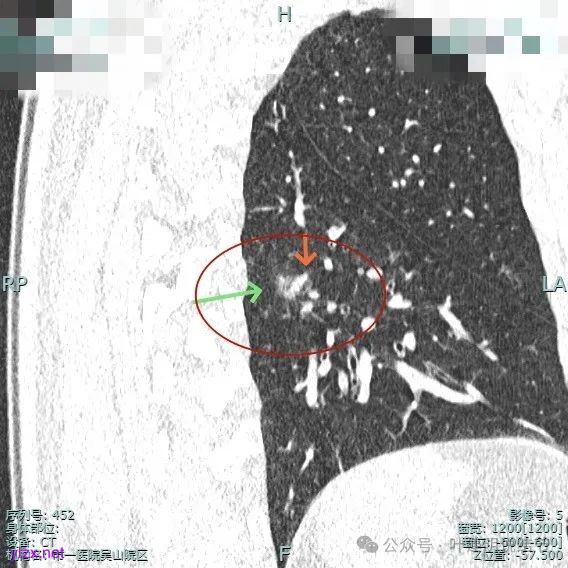

靶重建后见主病灶密度不均,灶内混合密度,整体轮廓较为清楚,表面不平,整体有一定膨胀感。

主病灶实性成分明显,表面有毛刺,边缘不平毛糙;次病灶密度纯且淡,轮廓清楚。

表面有浅分叶征,整体轮廓清。

主病灶混合密度,血管进入;次病灶小且淡,但轮廓清。

主病灶血管进入,灶内空泡,表面浅分叶,整体轮廓较清。